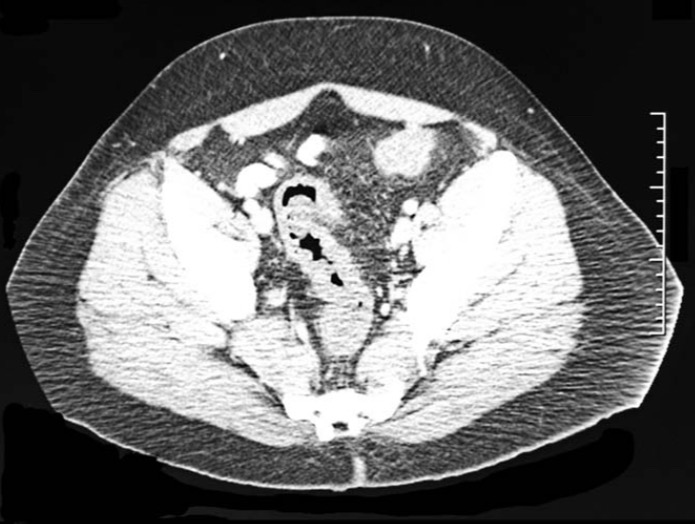

Компьютерная томография малого таза, демонстрирующая утолщение стенки сигмовидной кишки без признаков перфорации.